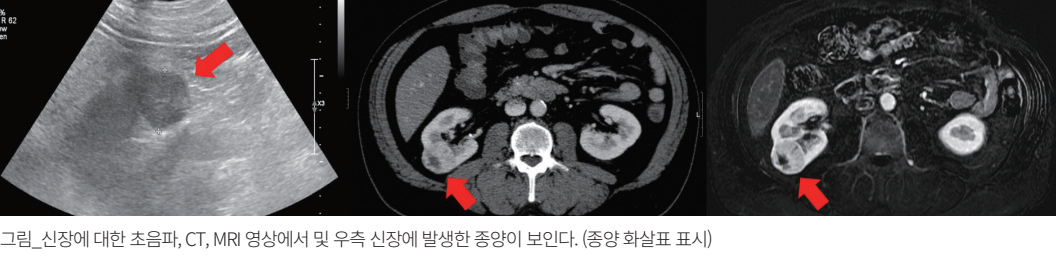

비뇨기는 신장, 요관, 방광, 그리고 요도와 같이 소변을 생성하고 체외로 배출하는 신체 기관이며, 넓은 의미로는 고환, 부고환, 그리고 음경과 같은 남성 생식기관 및 정낭과 전립선 같은 부속 생식기관을 포함한다. 비뇨기에는 다양한 종류의 암 질환이 발생할 수 있으며, 노령 인구 증가로 인해 질환의 빈도가 전반적으로 증가하고 있다. 비뇨기에 발생한 암 질환을 진단하고 적절한 치료 방법을 결정하기 위해 다양한 영상의학적 기법 및 지식을 활용하고 있다. 초음파, CT(컴퓨터단층촬영), 그리고 MRI(자기공명영상) 기법이 대표적이다.

진단 목적의 초음파는 인체에 무해하기 때문에 암 질환의 조기 발견을 위한 건강검진에 많이 활용하고 있으며, 비뇨기에서도 일차적으로 활용할 수 있는 유용한 검사입니다. 하지만 초음파는 신체 내부의 상태, 특히 장에 있는 공기로 인해 판단하기 어려운 장기나 질환이 있습니다. 예를 들어 혈뇨가 있는 사람의 경우 요로의 결석이나 암 질환을 의심할 수 있는데, 초음파로는 요관의 질환을 판단하는 것이 매우 제한적입니다. 그리고 초음파에서 비록 암이 의심되었어도, 암을 닮은 양성 질환, 초음파에서 암처럼 보이지만 실제로는 가짜 병변인 경우도 비교적 흔합니다. 따라서 초음파에서 비뇨기계 암 질환이 의심되는 경우, 대부분 CT(컴퓨터단층촬영) 또는 MRI(자기공명영상)를 이용한 추가 진단이 필요합니다.

인체의 내부 장기에 대한 단면 영상을 구현할 수 있습니다. 정상 구조물과 병변이 잘 구분되며, 장비의 발달로 비교적 넓은 신체 부위를 빠르게 촬영할 수 있습니다. 따라서 암 질환의 진단 및 추적 관찰에 있어 CT의 활용도는 매우 높습니다. 하지만 CT는 장비의 원리상 환자가 방사선에 피폭됩니다. 따라서 건강검진의 목적으로 CT를 남용하는 것은 옳지 못하며, 비뇨기 암 질환을 의심할 수 있는 증상이나 혈액 검사 소견이 있는 경우, 또는 이미 진단된 암 질환의 병기 설정이나 치료 후 재발 여부를 판단하고 치료 반응을 평가하는 등의 활용 목적이 뚜렷한 경우 시행합니다.

MRI는 자기장을 활용하여 인체 조직의 특성을 분석하고 인체 구조 및 비정상적인 상태를 영상화할 수 있는 발전된 최신 영상 기법의 하나입니다.

CT와 달리 방사선 피폭이 없어서 비교적 안전합니다. 하지만 MRI의 단점은 검사에 드는 시간이 길고 비용이 상대적으로 높다는 점입니다.